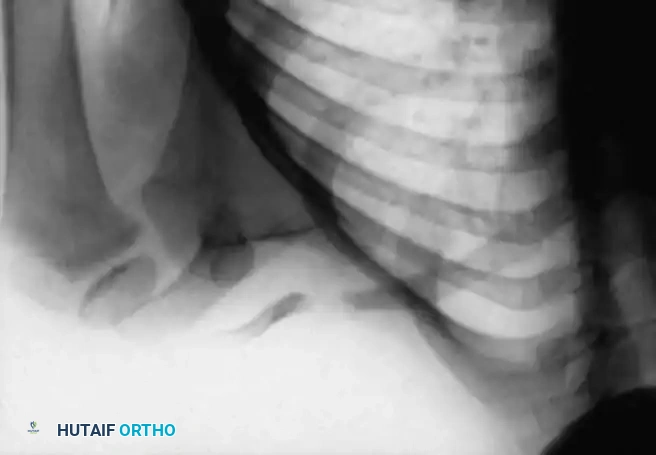

The radiographic findings of a congenital dislocation are pathognomonic and serve to differentiate it from traumatic dislocations.

In a traumatic dislocation, the radial head is typically normal in shape, and the ulna may show signs of a healed fracture or plastic deformation. In congenital cases, the radial head is dysplastic (dome-shaped), the capitellum is hypoplastic, and the ulna exhibits adaptive bowing.

* Radial Shaft Hypertrophy: The radial shaft is abnormally long relative to the ulna.

* Ulnar Bowing: The ulna is usually abnormally bowed to accommodate the over-lengthened radius.

* Direction of Dislocation: The radial head is most frequently dislocated posteriorly, though anterior and lateral dislocations can occur.

* Dysplastic Radial Head: The head is rounded and dome-shaped, showing little to no central depression (fovea) for articulation with the capitellum. It is usually significantly smaller than normal.

* Capitellar Hypoplasia: The capitellum is often small and flattened due to the absence of normal articulating forces during skeletal development.

* Absent Radial Notch: The radial notch of the proximal ulna is typically small, dysplastic, or entirely absent.

* Ectopic Ossification: Occasionally, areas of heterotopic ossification are present in the soft tissues surrounding the radial head.